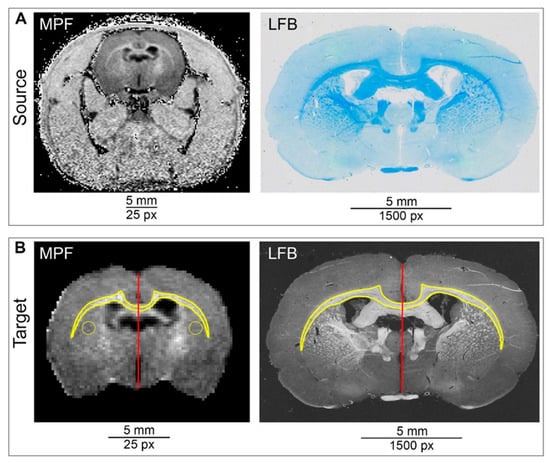

2.4. ROI Transformation Protocol (ROIT Method)